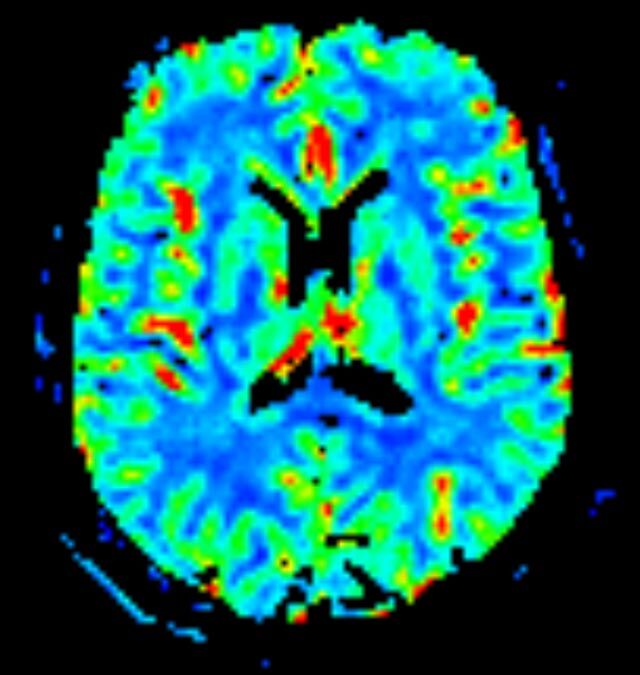

Kopf

• akute Schlaganfalldiagnostik und chronische Durchblutungsstörungen

• entzündliche Prozesse des Gehirns oder der Gesichtsweichteile

• Tumore, ggf. mit Spektroskopie

• Abklärung Schwindel, zentrale Sehstörung, Kopfschmerz

• Metastasenverdacht

• Multiple Sklerose

• Abklärung Hirnnerven, Schädelbasis inkl. Hypophyse

• Abklärung Kleinhirn, Hirnstamm, Halsmark

• intrakranielle Gefäße (Abklärung Verschluss, Stenose, Aneurysma)